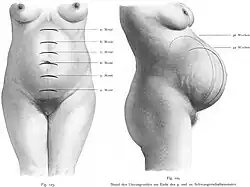

Durante a gravidez, o organismo materno passa por diversas adaptações e alterações fisiológicas fundamentais para sustentar o feto em crescimento e preparar o parto. Embora as alterações mais evidentes sejam as decorrentes do aumento do volume uterino, ocorre também um grande número de alterações hormonais, metabólicas, bioquímicas e anatómicas.[48]

Útero e placenta

O útero é um órgão de forma semelhante a uma pêra, que compreende uma extremidade inferior, denominada colo do útero (ou cérvix), adjacente a uma parte bolbosa maior, denominada corpo do útero. Numa mulher não grávida com cerca de vinte anos, o útero mede aproximadamente sete centímetros de comprimento e pesa cerca de 30 gramas. No termo de uma gravidez, o útero mede cerca de 30 cm de comprimento, pesa cerca de 1 200 g e tem uma capacidade líquida entre 4 e 5 litros. Este aumento significativo de tamanho durante a gravidez deve-se ao aumento da quantidade de fibras musculares, vasos sanguíneos, nervos e vasos linfáticos na parede uterina. A própria fibra muscular aumenta entre cinco a dez vezes de tamanho e o diâmetro dos vasos sanguíneos e capilares aumenta consideravelmente. Durante as primeiras semanas de gestação, a forma do útero mantém-se inalterada. Por volta da 14ª semana, o corpo do útero apresenta a forma de uma esfera achatada, enquanto o colo se apresenta muito mais macio e adquire um rolhão mucoso que o protege. À medida que o feto em crescimento vai exigindo mais espaço, o corpo do útero alonga-se e a parede torna-se mais fina. A determinado ponto, sobe para além da pélvis e preenche a cavidade abdominal, exercendo pressão no diafragma e nos outros órgãos. Com a aproximação da data de termo, a cabeça do feto começa a descer em direção à pélvis, fazendo com que todo o útero acompanhe o movimento, dando origem ao que popularmente se denomina "descida da barriga". No entanto, este processo pode só ocorrer durante o parto ou não ocorrer caso o feto esteja numa posição fora do esperado. No termo da gravidez, o colo do útero vai-se tornando gradualmente mais fino e macio e, durante o parto, dilata para a passagem do bebé.[1]